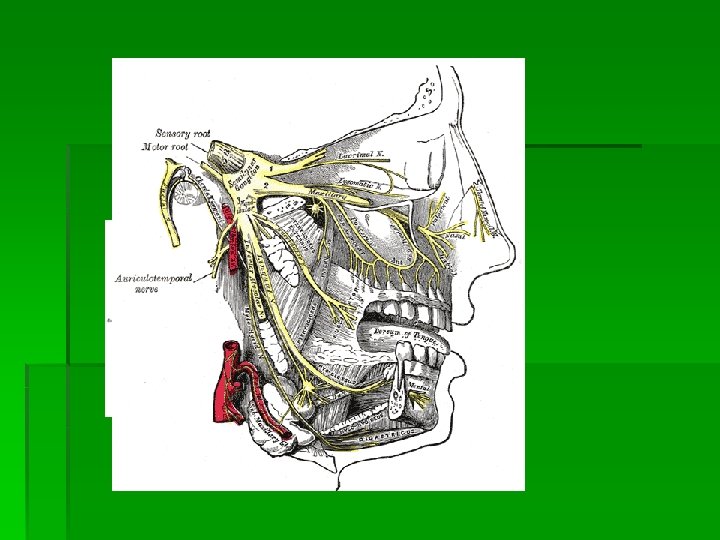

CLASIFICACION

CLASIFICACION